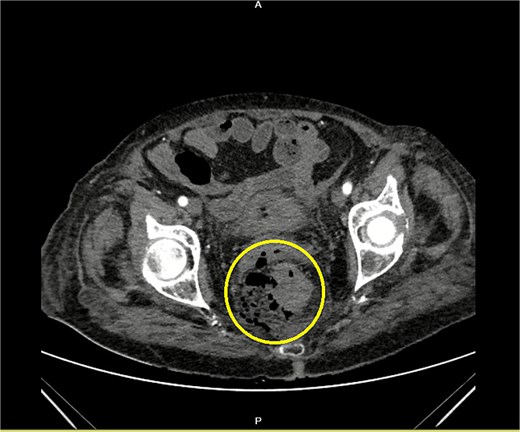

An 84-year-old female patient presented with massive hematochezia without a physiologic bowel movement that day. Previous comorbidities reported were hypertension and diabetes mellitus. Two months ago, the patient reported being treated with blood units due to unexplained anemia, with no further diagnostics conducted. On admission, the abdominal physical exam was unremarkable. The digital rectal exam revealed blood in the rectum. The laboratory test revealed a low erythrocyte count of 2.36 × 106/μL (3.93–6.08), Hemoglobin level of 7.8 g/dL (11/2–17.5), Hematocrit % of 24.3 (34.1–51), Leucocyte count of 18.1 × 103/μL, Neutrophil % of 85.7 (34–71.1), serum glucose level of 24.5 mmol/L (3.3–5.6), and albumin level of 33 g/L (34–50). The patient was admitted for resuscitation and further investigation. Two units of blood were given. A diagnostic colonoscopy performed the next day revealed sigmoid diverticulosis and a solitary mid-rectal diverticulum with a wide opening and necrotic bottom (Fig. 1). The patient presented with two episodes of fever, reaching a maximum of 38.3°C. On the third day of admission, an elevated level of procalcitonin (27 ng/mL), (0.05–0.1), Leukocytosis of 23.0 × 103/μL, and a CRP level of 248 mg/L (0–5) were noted. The general condition of the patient slightly worsened, and the repeated abdominal physical exam remained unremarkable. A contrast-enhanced abdominal computerized tomography showed free air around the mid rectum in the pelvis (Fig. 2) with cranial retroperitoneal extension (Fig. 3). Emergency laparotomy was indicated. No signs of peritonitis were noted. After rectal mobilization and dissecting distally, a gas bubble occurred. Further distal dissection revealed a small abscess on the anterolateral wall with a visible opening in the rectal wall. A low Hartmann procedure was performed (Fig. 4). The postoperative period was uneventful. The length of hospital stay was 9 days. Pathology analysis confirmed the presence of a solitary rectal diverticulum perforation with accompanying diverticulitis.

Contrast-enhanced CT of the pelvis showing free air around the rectum with a visible defect of the rectal wall (encircled).